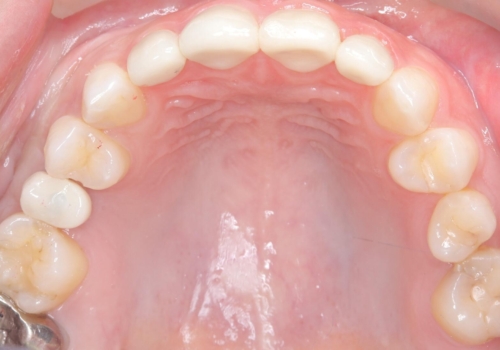

インプラント埋入手術は1回で全て行い、2ヶ月後にはセラミック治療で、審美回復と機能回復をしました。

来院回数が少なく、しっかり食事もできるとの事で非常に喜んで頂けました。